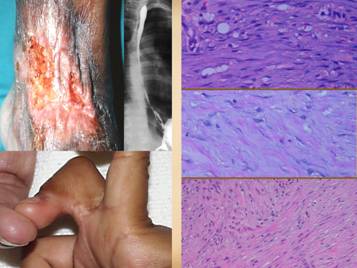

9

Here are two examples of common mechanical ulcers with no pathology, just adverse mechanics.  Upper: a young boy with a simple trauma laceration of the ankle which became a chronic ulcer after a period of non-specific care.  Perforation of the skin into the malleolar bursa is one of the mechanical factors affecting the problem, and perforation into the tibialis posterior tendon sheath, with gliding of the tendon is the other problem.  Conventional principles of plastic surgery dictate that a flap is needed to restore the overlying tissue, but modern strategies and technologies give us opportunities to close this without autogenous flaps.  Tissue restoration with regenerative matrices is one good approach.  Another approach is to try using wound stimulatory therapies, successful here using PDGF.  For all of these methods, especially the non-operative ones, concurrent immobilization is mandatory to control the contrary motion and mechanics that are inhibiting the wound.  Lower: an adult spina bifida patient with a chronic pseudarthrosis in the lower thoracic spine, at the site of an old fusion.  Open joints, real or false, are bursas or spaces that need surgery and immobilization.  The initial wound (left) was excised, including removal of the arthrosis enough to avoid bone-on-bone contact.  A catheter was left in this restricted space for the sake of good preparatory care prior to closure (irrigation with silver sulfadiazine, center).  When ready for closure, the void was filled with a regenerative matrix, and the skin was also reconstructed with the same matrix, in lieu of conventional flaps (Integra collagen-gag matrix).  A TLSO (thoraco-lumbo-sacral orthosis, i.e. splint) was crucial for immobilization, and the wound healed completely.